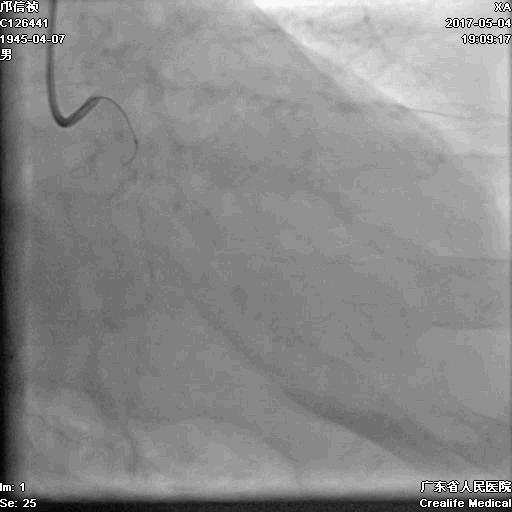

1.更换RG3导丝

2.GC送入普通导丝,保护LM

RCA闭塞段球囊扩张后IVUS

支架术后造影结果

支架术后IVUS